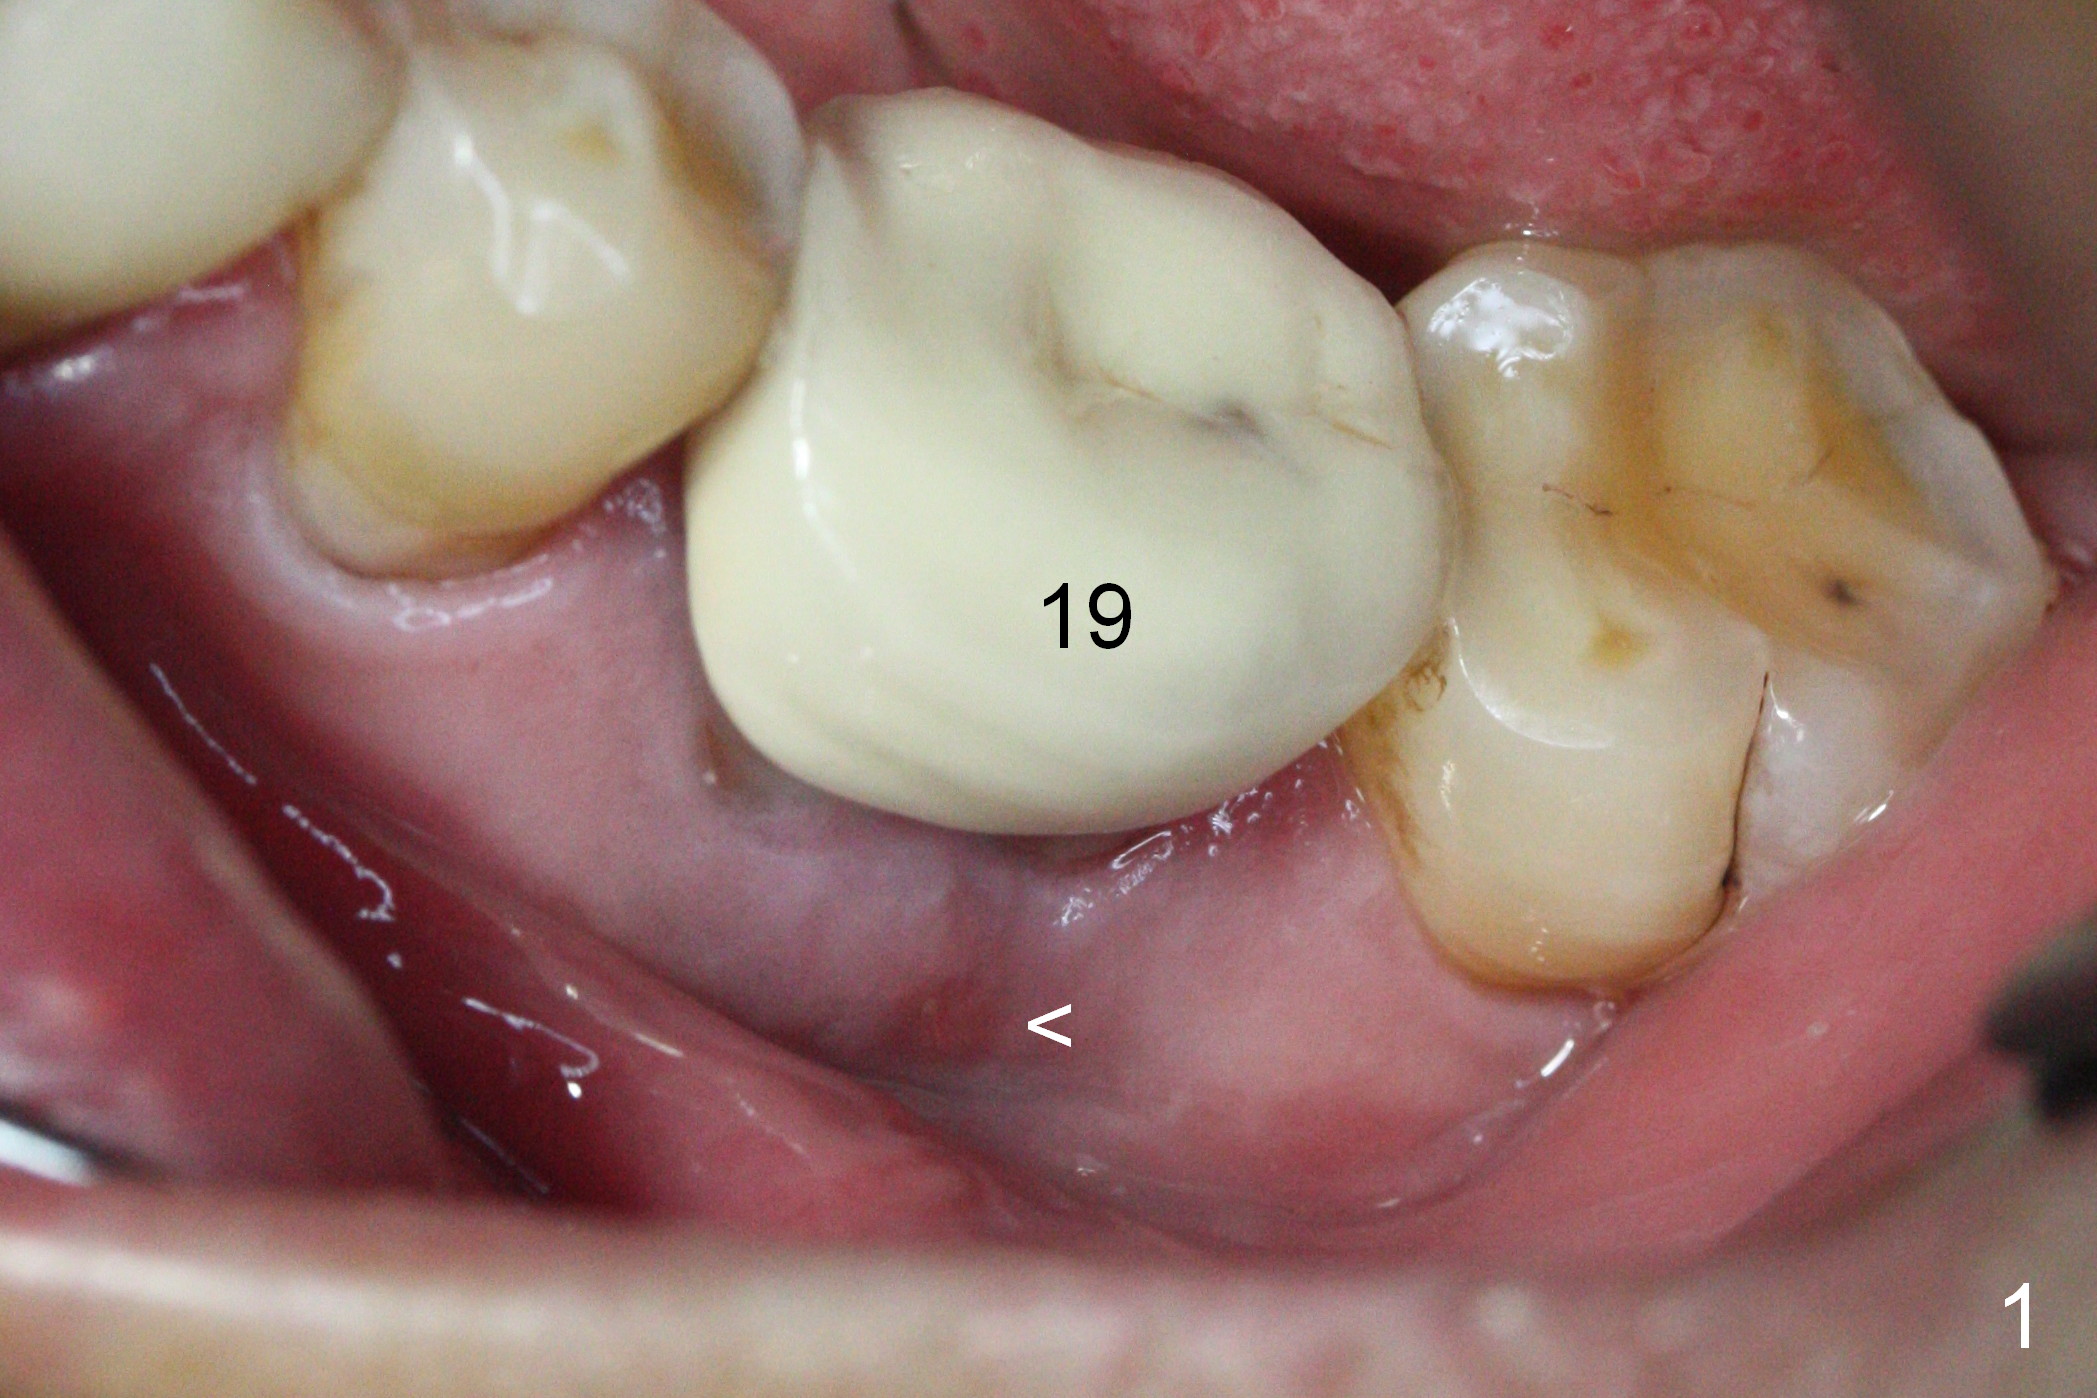

The asymptomatic tooth (#19) has a midbuccal fistula (Fig.1 <). The mesiobuccal pocket is 10 mm with purulent discharge from the sulcus (Fig.2,3). The mesiobuccal wall defect is confirmed when the tooth is extracted. Osteotomy is initiated lingually in the septum following septal crestoplasty (flattening) (Fig.4: using 1.6 mm drill for 9 mm). Since the lingual portion of the osteotomy is higher, it is difficult to use drill with stopper. For the narrow septum osteotomy, multiple drills are used sequentially (Fig.5 after 4.3 mm drill). A 4.5x11 mm dummy implant is placed (Fig.6) apparently too deep. When a 5x11 mm IBS implant is being placed, the depth is tightly controlled (Fig.7). The implant is apical to the lingual crest, whereas there is ~ 2 mm implant exposure buccally. That is, there is a large gap mesiobuccally (Fig.8), which is filled with .5-1.5 mm allograft (Fig.9 *). A 6.5x5.7(3) mm abutment (A) is placed and trimmed for an immediate provisional (Fig.10 P). The lacerated buccal gingiva is sutured as well as application of Perio Glue.